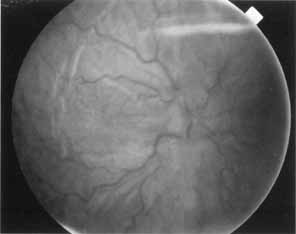

Choroidal detachment may accompany hypotony from overfiltration, but more commonly the fundus exhibits chorioretinal folds and disc edema (Fig. 2), with a reduction in visual acuity to the 20/400 range. This was first described by Dellaporta,15 but the term hypotony maculopathy was coined by Gass.16 Presumably, the sclera shrinks from the low intraocular pressure, leaving the choroid wrinkled like an unstretched carpet. Cystoid macular edema may also coexist with hypotony maculopathy.17 Hypotony maculopathy is more common in young myopes after filtering surgery. It is not known with certainty how long hypotony maculopathy may be allowed to exist before permanent visual loss occurs. It is the author's opinion that 3 months is a reasonable period of time to wait before further surgical intervention is indicated. However, one case of hypotony maculopathy of 7 years duration improved from 20/200 to 20/30 vision after closure of a cyclodialysis cleft.18 Injection of autologous blood into the bleb has been described,19 but is not without risk.20 Resuturing the scleral flap is effective in reversing hypotony and restoring visual acuity while still maintaining some degree of filtration.21–26

Fig. 2 Chronic hypotony after filtering surgery with mitomycin C resulting in chorioretinal folds and disc edema.